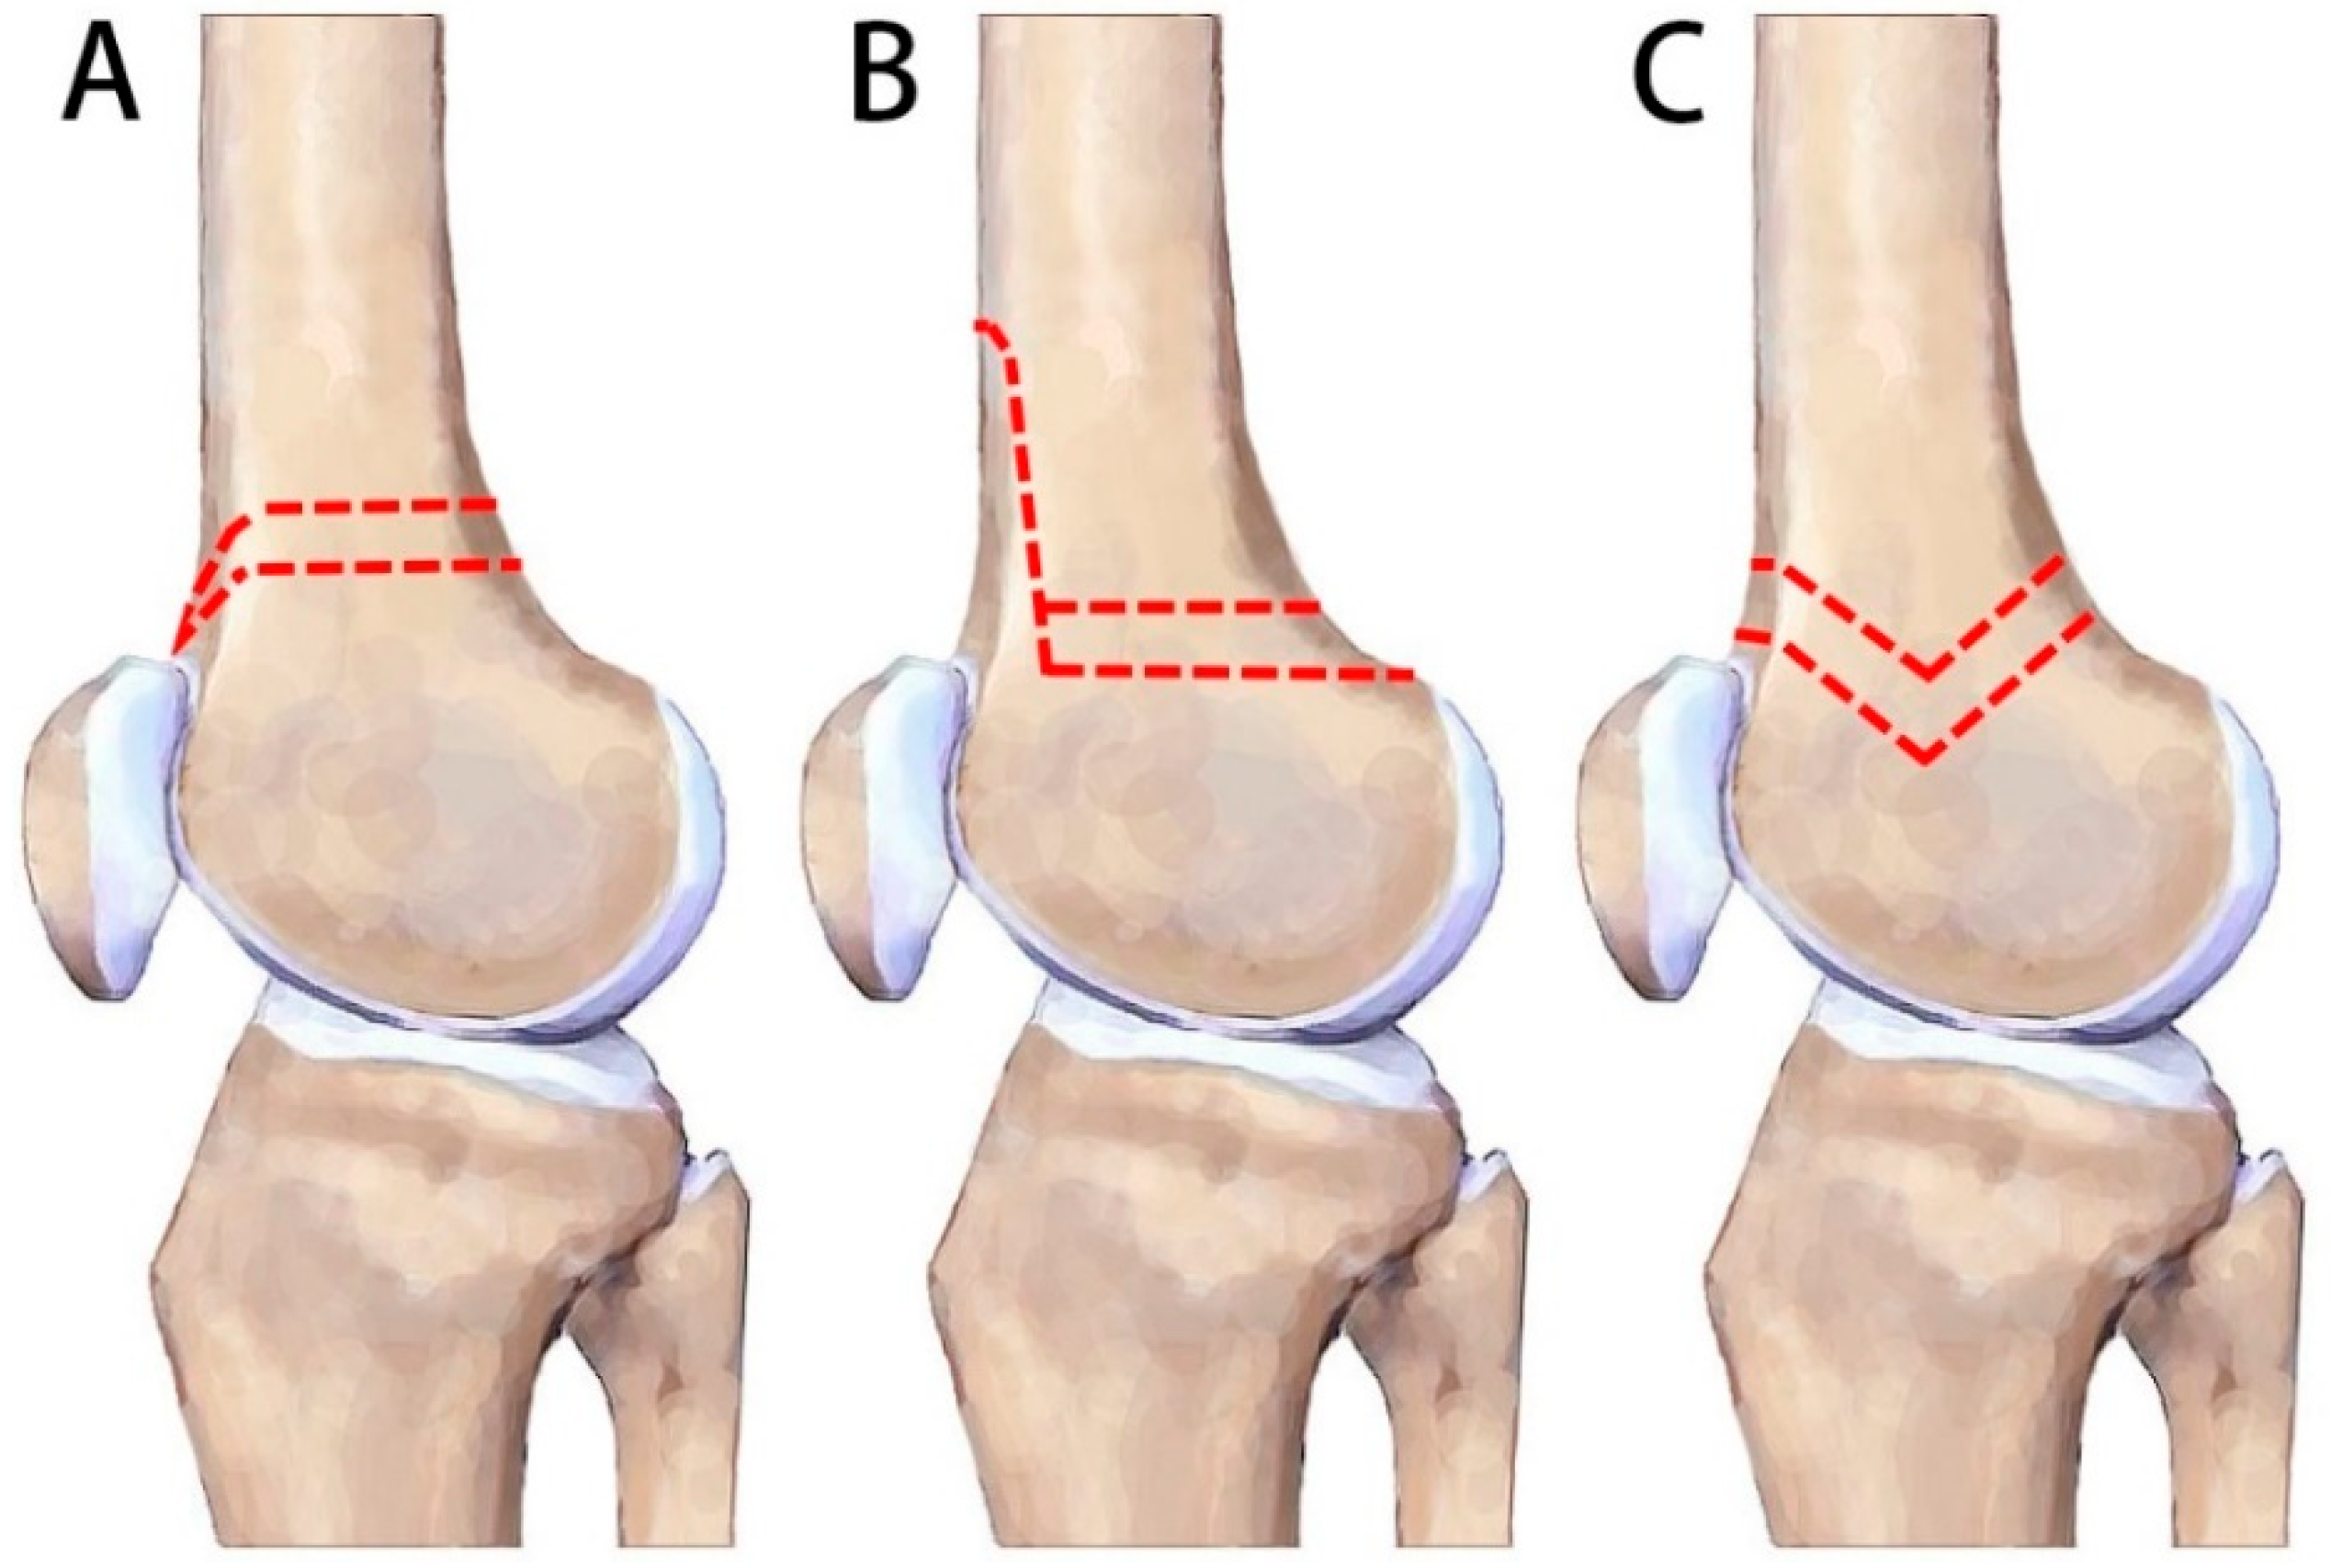

:1. Introduction

2.2. Surgical Technique